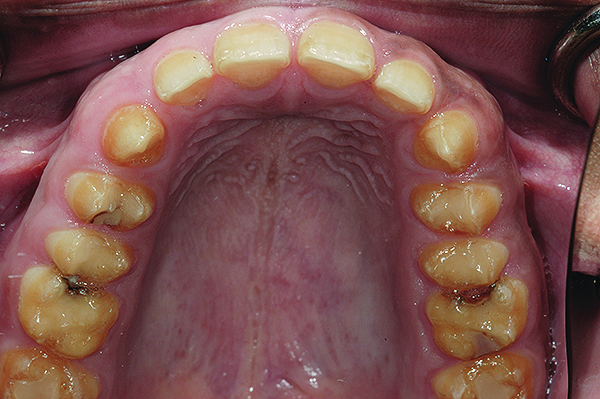

Figure 6. Preoperative maxillary occlusal view.

Figure 6